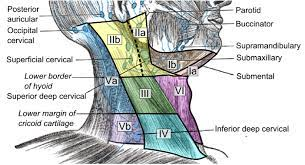

Lymphatic system

總圖

Nodes

Groups

- Level I

- the submental group (Ia), and the

submandibular group (Ib). - Level II

- the upper jugular lymph nodes

- level IIa – CN XI 前

- level IIb – CN XI 後

- Level III

- the middle jugular lymph nodes

- Level IV

- the lower jugular lymph nodes

- Level V

- all lymph nodes contained within the posterior triangle

- Level VI

- lymph nodes of the anterior (central) neck compartment

Tip

清除 I, II, III